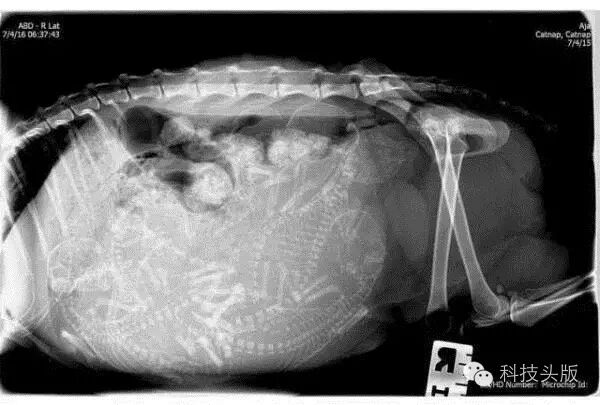

怀孕的南美洲栗鼠。萌萌的、小小的花栗鼠,也有这么大的能量,怀了这么多宝宝,好厉害,为它点赞!